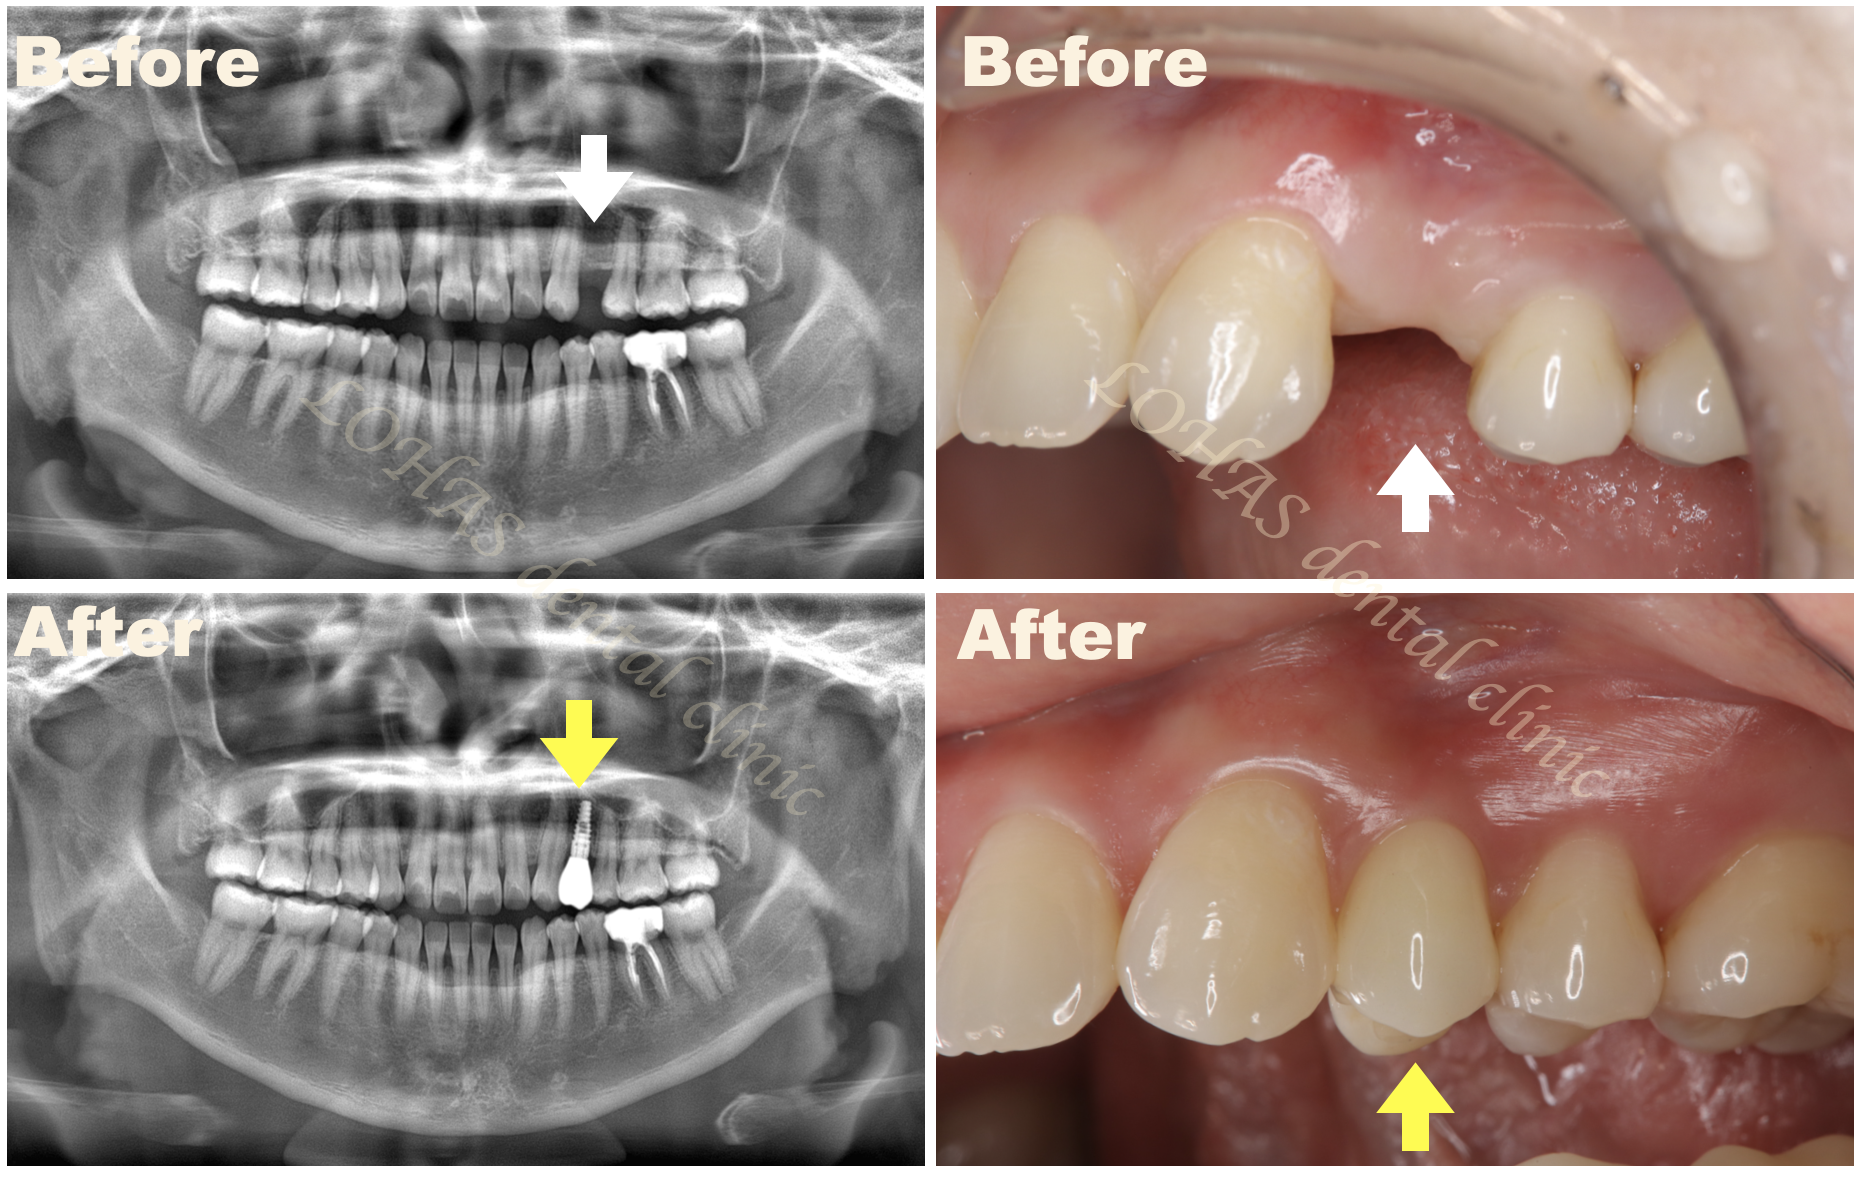

それでは実際に私が患者様に行ったソケットリフトの症例を見ていきましょう。

この患者様はすでにインプラント治療を終えて、美味しくお食事を取れるようになりました。